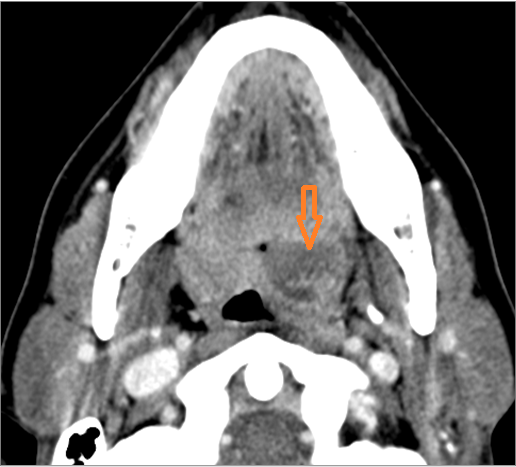

30-year old male with left facial swelling and tenderness mainly in the submandibular space. Primary clinical suspicion was an odontogenic infection.Exam

CT: Contrast- enhanced CT of the maxillofacial region and neck and related anatomy with images obtained in the balanced or venous vascular phase to ensure optimal visualization of both arterial and venous structures as well as possible reactive changes around infected collections. 0.5-3.0 mm thick sections were obtained in the axial plane and reformatted 3D and/or in the coronal and sagittal planes and viewed inter actively in 3 dimensions at the computer work station.